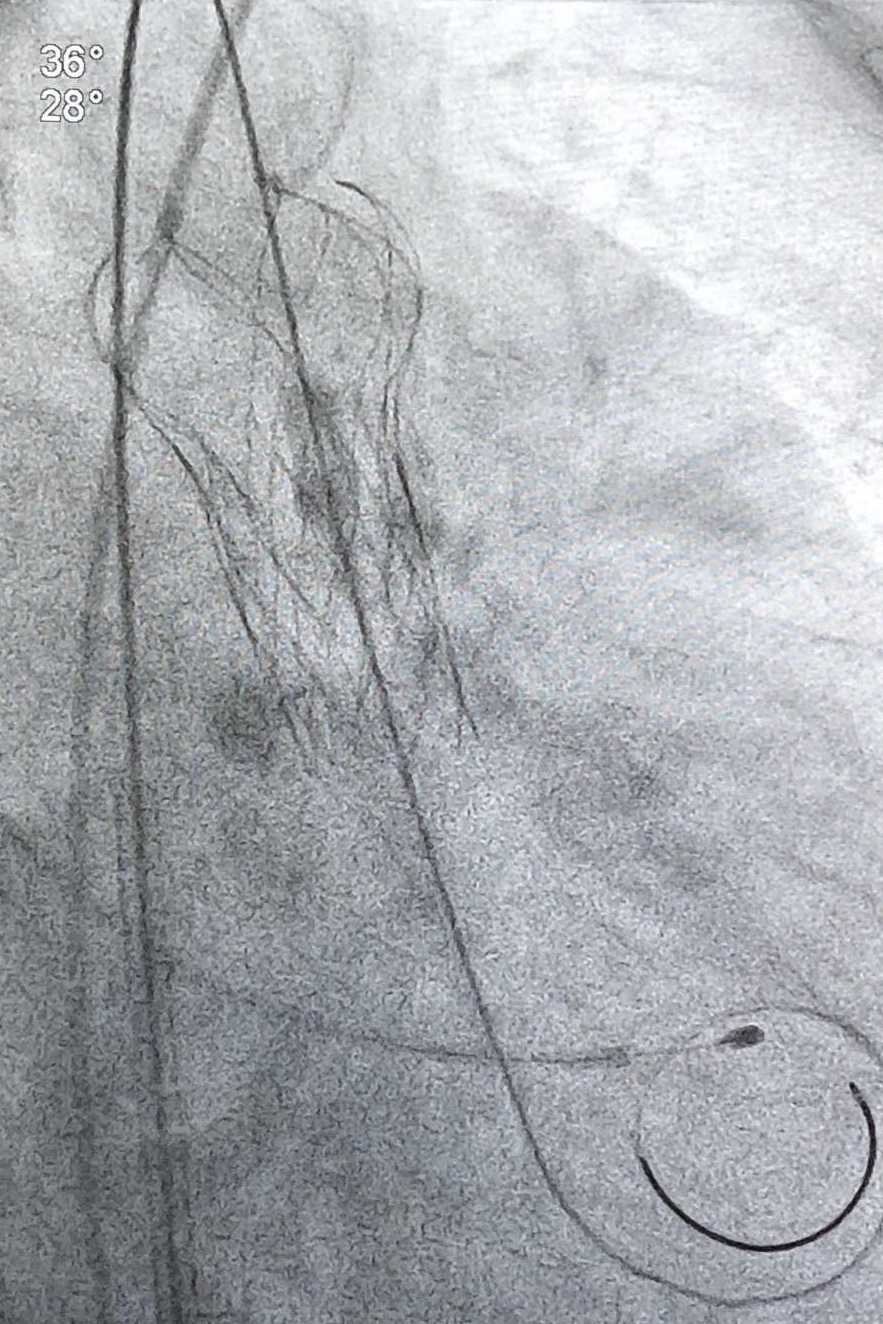

主動脈瓣植入后

10月25日上午9時,手術正式開始。手術由醫院心血管內科陳見紅、孫立平、苗柳三位副主任醫師實施,銀劍斌、陶林副主任及麻醉科、重癥醫學科、超聲醫學科專家全程支持。醫生首先完成臨時起搏器植入術后,經右橈動脈完成前降支支架植入術。隨后,醫生在患者大腿處切開一個直徑不到1厘米的小口,穿刺進入股動脈,置入鞘管,然后送入導絲建立軌道,再小心翼翼地將人工心臟瓣膜通過導絲軌道,精準輸送到預定位置。中午時分,手術順利完成,患者各項生命體征正常。術后第二天,老人順利轉出心內重癥監護室,回到普通病房進行后續治療,目前已經可以輕微活動,恢復良好。